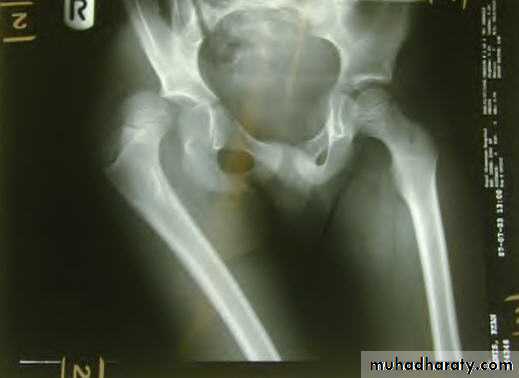

INTRA CAPSULAR FRACTUREfracture neck femur

The femoral neck is the commonest site of fractures in the elderly.

Mostly occur in women between 70-80 decades.

Pathological anatomy and classification

The most useful is that of garden which is based on amount of displacement apparent in the pre-reduction x-ray of the neck femur.

:Radiological classification

GRADE 1

:the femoral head is in its normal position or tilted into valgus and impacted on the femoral stump.